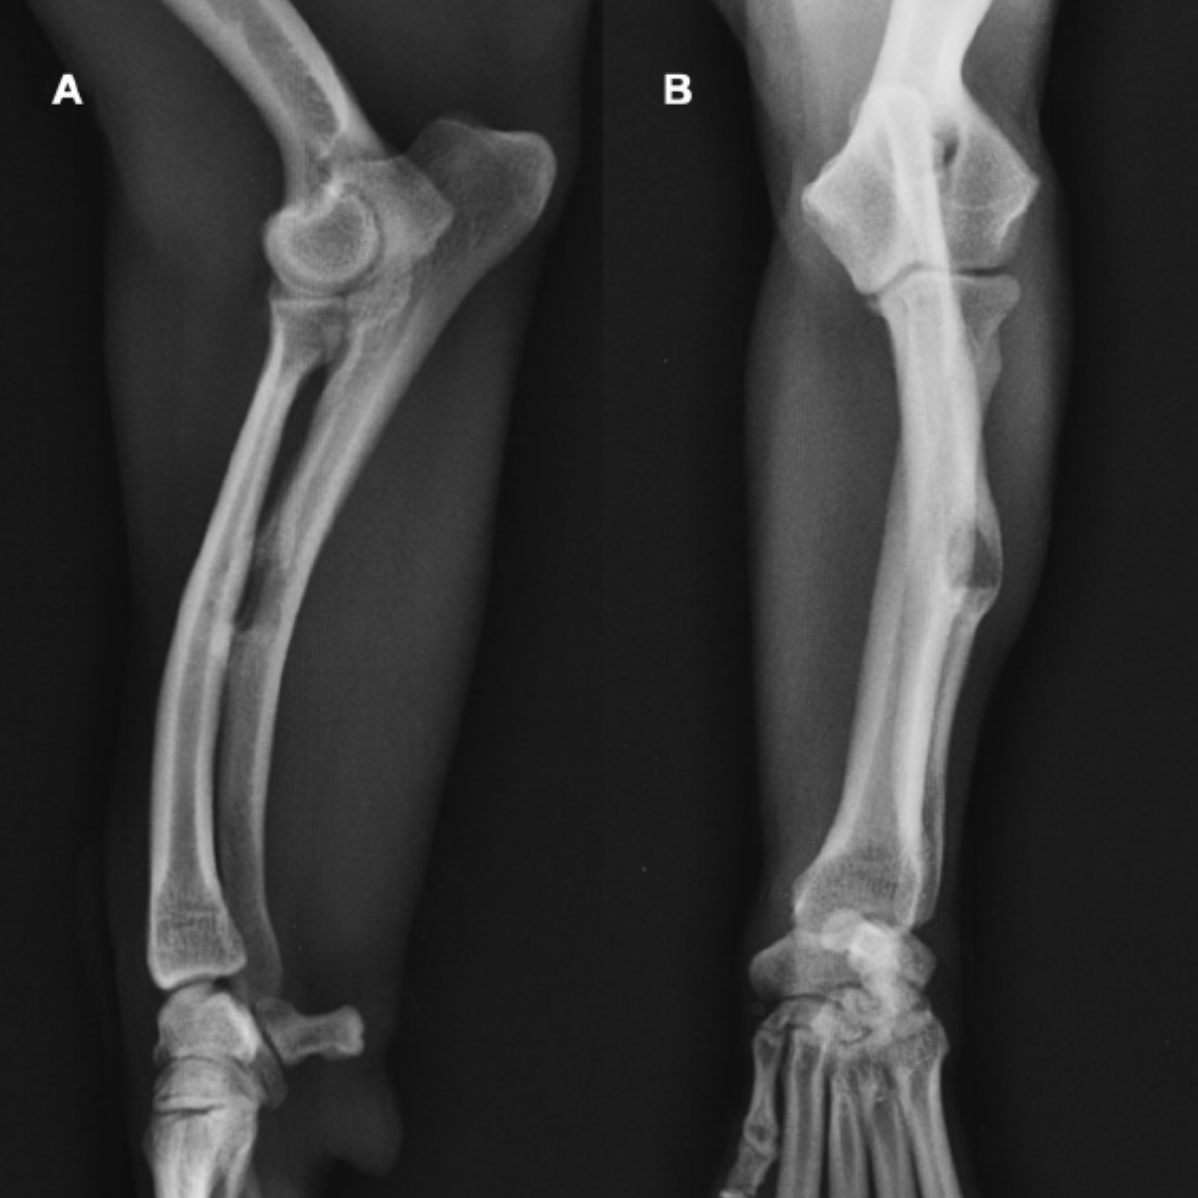

What is the most likely diagnosis?

Radioulnar ischemic necrosis (RUIN)